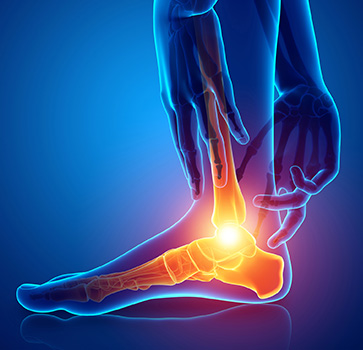

Heel spurs

A heel spurs is a foot condition created by a calcium deposit causing a bony protrusion on the underside of the heel bone. Heel spurs often start in the front of your heel and eventually affect other parts of your foot. Although heel spurs are often painless, they can cause heel pain. They often start in the front of […]